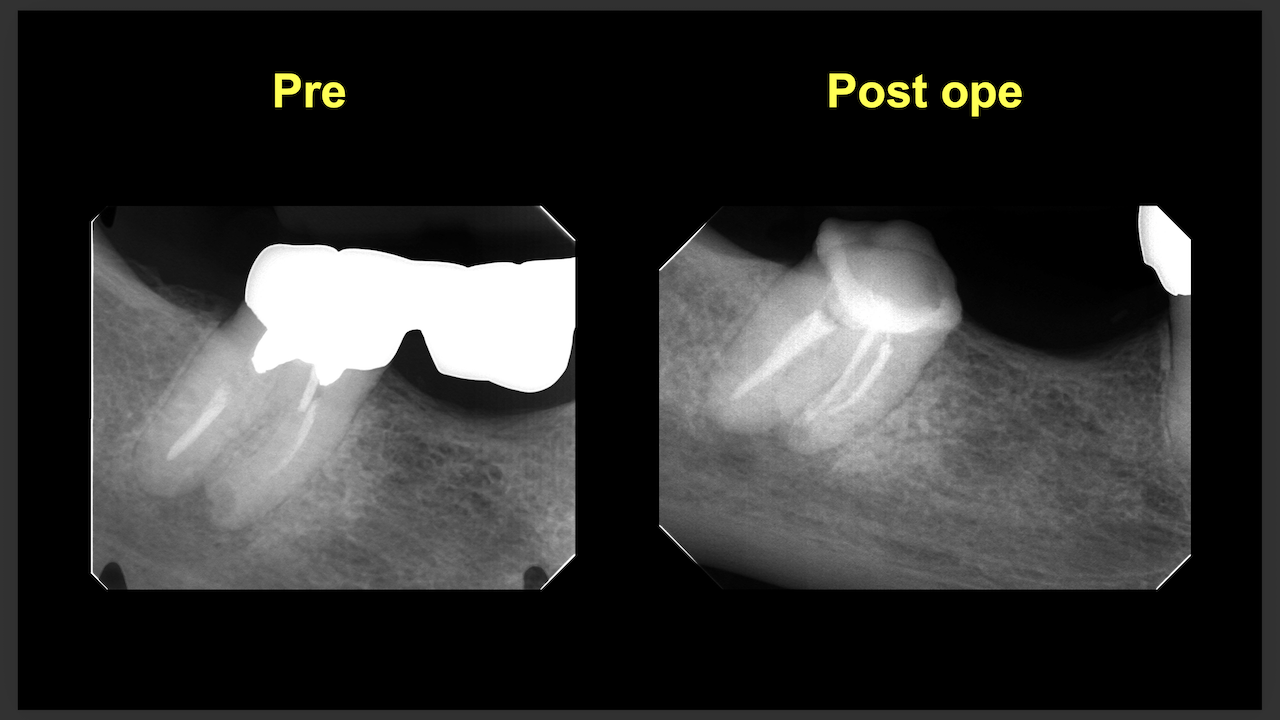

次は東京から参加のN先生。

術前/術後を比較した。

#29

#4

ラバーダム防湿をして行った根管治療の威力がわかったと思う。

素晴らしいケースだ。